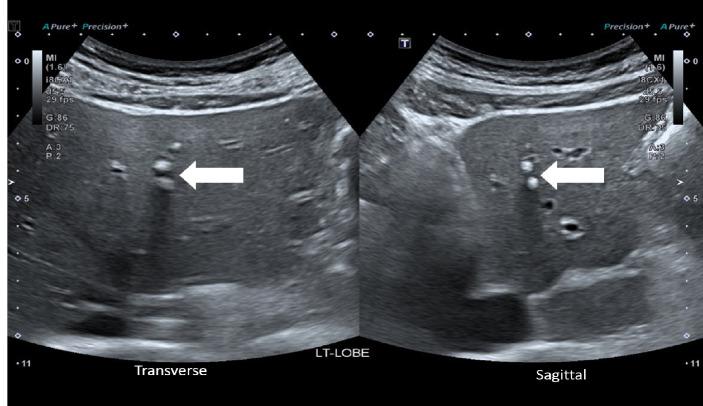

The study population was 4,337 villagers in Northern Thailand with a 5-year abdominal US surveillance. Patient demographics data and ultrasound findings of calcifications/granulomas, periductal fibrosis, and diffuse bile duct dilatation were included. A logistic regression model was used to determine significant predictors.

There were 4,225 people included with an average age of 45.49±7.66 years. Prevalence of calcifications/granulomas, periductal fibrosis, and diffuse bile duct dilatation detected on baseline sonographic surveillance was 11.7%, 20.5%, and 11.3%, respectively. The univariate analysis for significant predictors for CCA include age (Relative Risk; RR = 1.12), family history of CCA (RR = 2.29), periductal fibrosis (RR=2.38), and diffuse bile duct dilatation  (RR = 7.59). The multivariate analysis the independent predictors were age (RR = 1.12), family history of CCA (RR = 1.92), and diffuse bile duct dilatation (RR = 5.94), respectively.

The sonographic predictor for CCA surveillance in endemic areas is diffuse bile duct dilatation.  Age and family history of CCA are also helpful clinical markers.